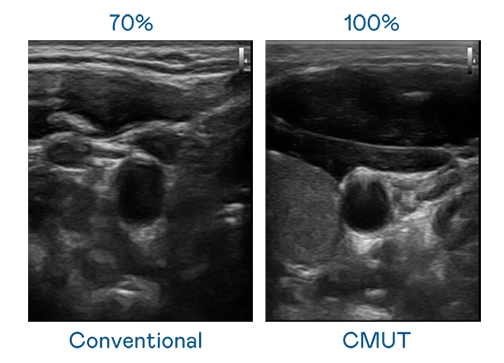

CMUT 技术是一种用电容式微机电元件来产生超音波讯号的技术。与传统 PZT 压电式技术相比,CMUT 频宽增加 30%,更宽频的超音波讯号让影像解析度大幅提升,是实现高影像品质医疗超音波扫描、促进精准医疗发展的关键技术。

大频宽带来超清晰影像

超音波影像的解析度高低,首先取决于探头能发出的讯号频宽。凯发娱乐 CMUT 可提供高清晰的超音波讯号,提供高频宽、高灵敏度、影像纹理细节更高的超音波影像,协助医护人员缩短影像判读时间及利用精准的医疗影像进行诊断。